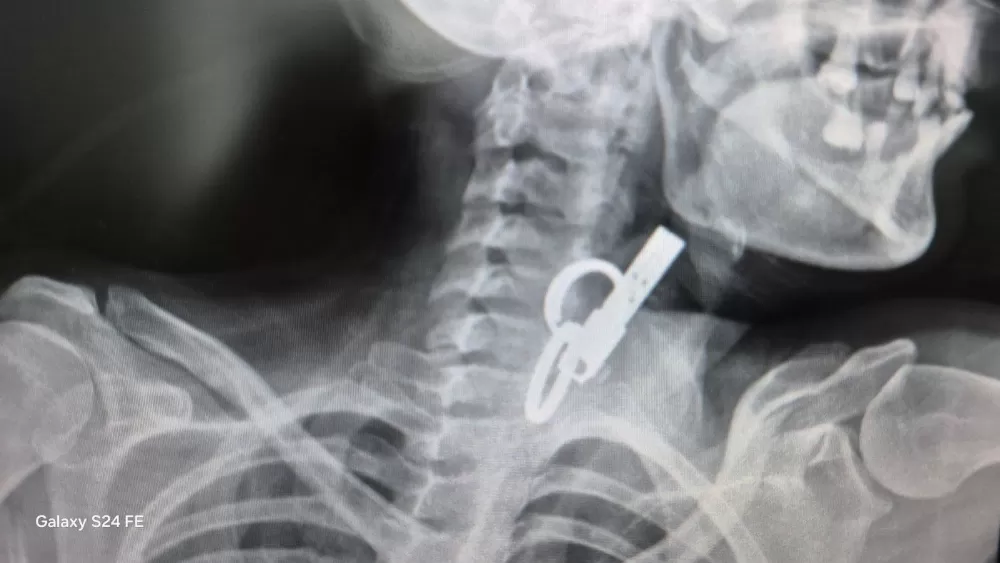

На Тернопільщині лікарі дістали ключі з організму пацієнта

У Гусятинській комунальній лікарні медики провели унікальну маніпуляцію та врятували пацієнта, який випадково проковтнув ключі.

Завдяки майстерності лікарів та наявності сучасного обладнання, велике стороннє тіло вдалося дістати зі стравоходу без жодного розрізу. Операцію виконали малоінвазивним ендоскопічним методом. Саме завдяки їхній злагодженій роботі вдалося уникнути традиційного хірургічного втручання та тривалої реабілітації пацієнта. Про це розповіли у КНП “Гусятинська КЛ” Гусятинської селищної ради.

Наразі чоловік почувається задовільно. Після короткого перебування в реанімації його перевели до загальнохірургічного відділення, де він залишається під наглядом фахівців. Лікарі зазначають, що стан хворого стабільний.